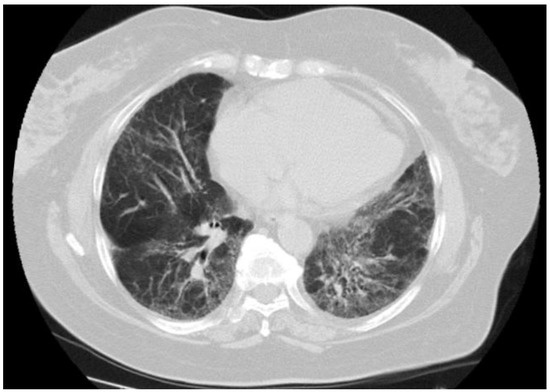

Figure 2.

NSIP pattern in a 70-year-old female with PBC who died from progressive respiratory failure.

3.5. Follow-Up

Repeated chest HRCT was conducted in 34 patients with ILD at an interval of 3–6 months. Immunosuppressive agents were started in case of radiological and/or clinical deterioration of ILD. A total of 16 patients were treated for ILD with azathioprine or methotrexate in combination with systemic glucocorticoid. Improvement in chest HRCT was shown in 22 patients. It was spontaneous in eight patients (sarcoid-like pattern in three, subclinical ILD in three, and OP in two) or induced by immunosuppression in 14 patients (sarcoid-like pattern in eight, OP in four, UnIP in two). ILD was stable in fivepatients who received no immunosuppression (subclinical ILD in fourand sarcoid-like pattern in one) and in two patients treated with immunosuppressive agents (sarcoid-like pattern and UIP). Radiological progression of ILD was found in five patients. Two patients with NSIP and UnIP died from liver cirrhosis complications before initiation of immunosuppressive treatment, whereas two patients with OP and UnIP had no respiratory symptoms and were clinically stable. One patient showed no ILD response to immunosuppressive agents. This was a 70-year-old female with NSIP (Figure 2) who developed severe pulmonary hypertension and died from respiratory failure. The autopsy revealed extensive interstitial pulmonary fibrosis consistent with fibrosing NSIP. During follow-up, only this patient died from ILD complications.